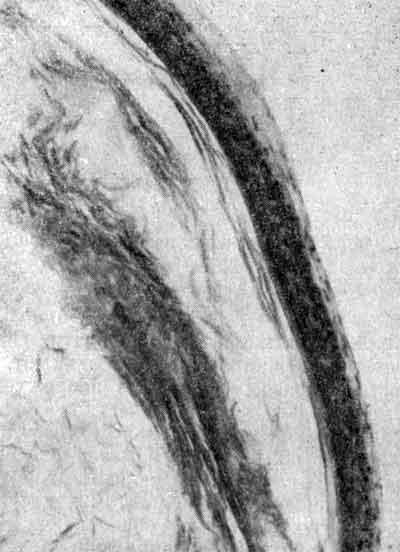

Капсула холестеатомы

Три удаленные холестеатомы